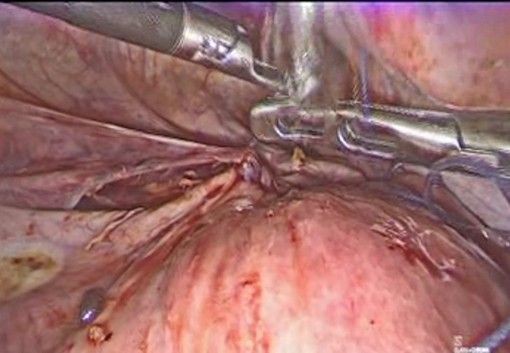

- Exposure of the lower uterine segment (Figure 3-5): the uterus is moved anteriorly or laterally to expose the utero-cervical junction (key anatomy: Anterior aspect of the lower uterine segment and cervix, vesicouterine fold, and peritoneal reflection of the bladder). The vesicouterine peritoneum is carefully incised and dissected, moving the bladder caudally to expose the anterior aspect of the cervix.

Figure 3: exposure of the lower uterine segment

Figure 4: Careful incision of the bladder peritoneum

Figure 5: the bladder I moved caudally